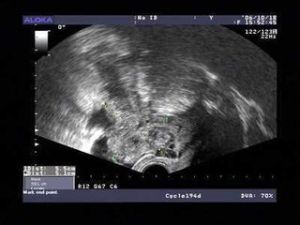

4、超聲檢查方便快捷,在盆腔積液檢查中對疾病的明確診斷方面有著明顯的優越性。相對於其他檢查診斷方法,超聲作為一種無創、無痛、方便的檢查手段,對各種原因引起的盆腔積液,可以根據超聲檢查,同時結合臨床資料及實驗室檢查,在明確診斷方面有著明顯的優越性。

5、彩超檢查,確定有無盆腔積液,進行彩超檢查是的檢查方法。可快速準確確定積液的量。

盆腔積液的位置多發生在子宮直腸陷窩等盆腔內位置較低處,婦科常用的有效檢查手段是B超,可以較準確的判斷積液的量。